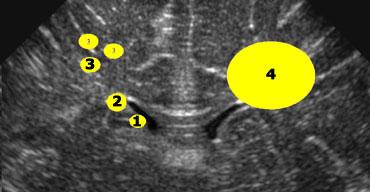

1+2 = nang tiêu mầm và giả nang, 3 = nhuyễn chất trắng quanh não thất dạng nang, 4 = nang do nhồi máu tĩnh mạch

Các loại nang

Khi phát hiện nang quanh não thất bên, điều quan trọng là phải xác định vị trí của chúng so với phần trên của não thất bên (xem hình).

- 1+2 = Nang tiêu mầm và Giả nang nằm dưới hoặc ngang mức phần trên của não thất bên.

- 3 = Nhuyễn chất trắng quanh não thất dạng nang (Cystic periventricular leukomalacia) chủ yếu nằm trên mức này.

- 4 = Nang do nhồi máu tĩnh mạch có kích thước lớn và có thể nằm trên, ngang hoặc dưới mức này.